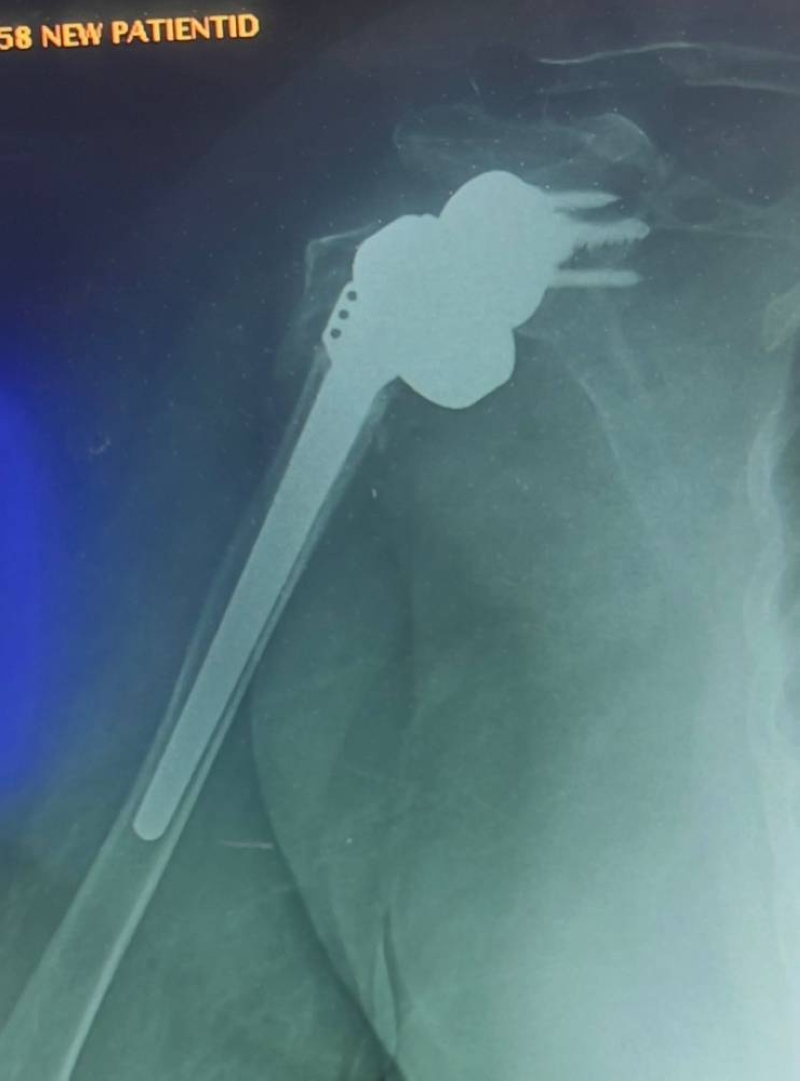

أعلن رئيس قسم العظام في مستشفى الفروانية الدكتور محمد مفيد عن إجراء أول عملية استبدال مفصل كتف كامل من النوع العكسي في المستشفى، تحت إشراف الدكتور بدر البشاره اختصاصي جراحة العظام وجراحة الكتف، وذلك لمريضة متقدمة في العمر بسبب كسر معقد ومتقدم في مفصل الكتف أفقدها القدرة على حركة المفصل.

وأوضح الدكتور مفيد في تصريح لـ «الراي» أن هذه العملية تعتبر من الجراحات المتقدمة في مجال جراحة مفصل الكتف، ونتائجها ممتازة خاصةً عند إجرائها في حالات الكسور المعقدة لكبار السن أو في حالات الخشونة المصاحبة لقطوع أوتار الكتف المزمنة.